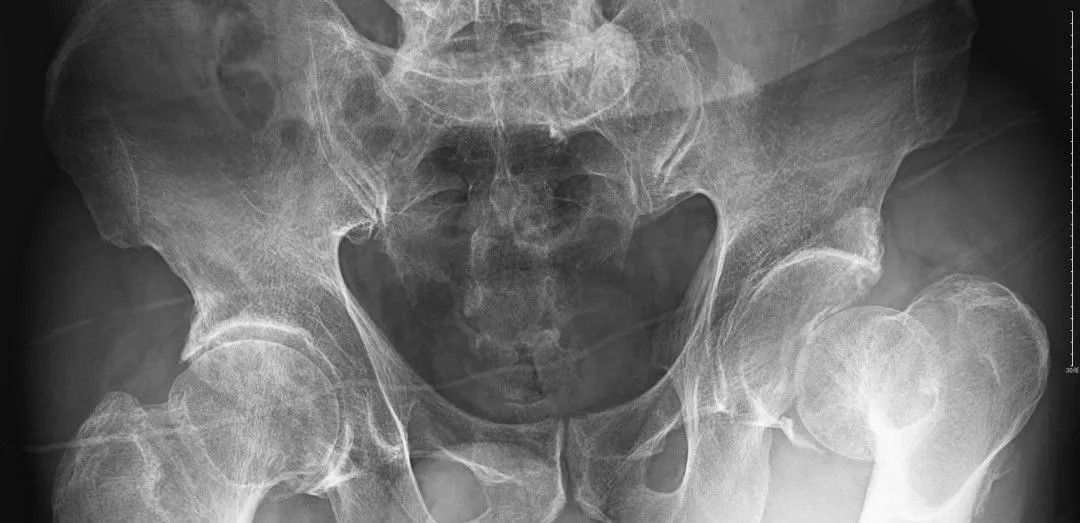

經(jīng)過(guò)王副主任認(rèn)真仔細(xì)的檢查,并結(jié)合X線攝片后,他告訴患者及其家屬:“周大爺是外傷導(dǎo)致的急性髖關(guān)節(jié)脫位、髖臼骨折!”一聽(tīng)脫位骨折了,患者及家屬焦慮萬(wàn)分,擔(dān)心手術(shù)給身體和經(jīng)濟(jì)帶來(lái)的巨大壓力。王副主任耐心告知周大爺一家人:“周大爺這種病情可以保守治療,用我們顧氏的正骨手法可以復(fù)位的,不需要開(kāi)刀,價(jià)格也實(shí)惠”。家屬聽(tīng)到不用做手術(shù),瞬間放心不少,表示非常愿意配合治療。

(術(shù)后復(fù)片  關(guān)節(jié)對(duì)位良好)